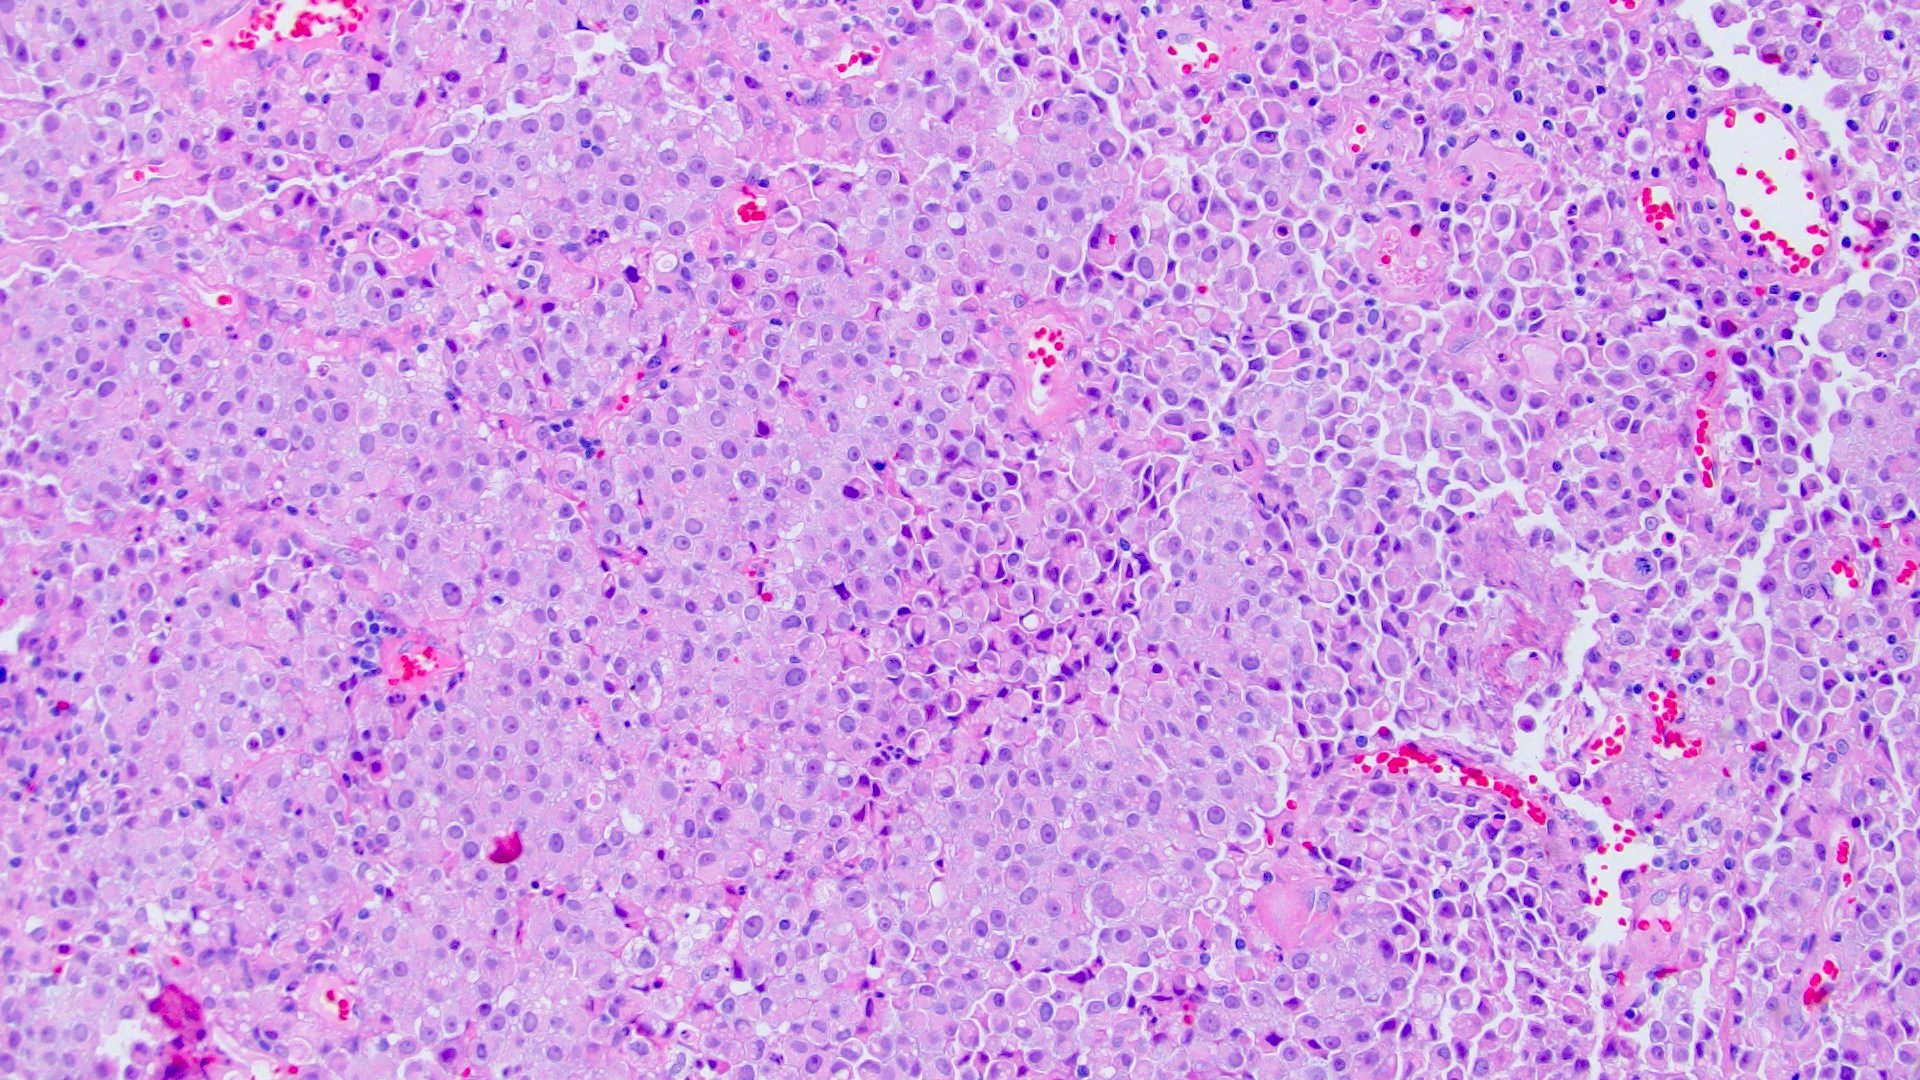

- Discohesive single cells with eccentrically placed nuclei and abundant eosinophilic cytoplasm

- Often deeply infiltrative but with minimal stromal reaction (Eur Urol Focus 2020;6:653)

- Further subclassified into classic, pleomorphic and desmoplastic subtypes:

- Classic: signet ring-like morphology, singly scattered and discohesive in loose aggregates forming cords (Hum Pathol 2019;90:27)

- Often mixed with other histologic subtypes; in 1 case series, 53% of PUC had mixed histologic subtypes (Am J Clin Pathol 2017;147:500)

- Despite resemblance to signet ring carcinoma cells, notably lack extracellular mucin, contrasting to signet ring adenocarcinoma (Acta Cytol 1991;35:277, Am J Surg Pathol 1991;15:569)

Microscopic (histologic) images

Contributed by Timothy Isaac Miller, M.D., M.A., Nicole K. Andeen, M.D. and Maria Tretiakova, M.D., Ph.D.

Contributed by Lisa Han, M.D. and Ricardo Lastra, M.D. (Case #510)